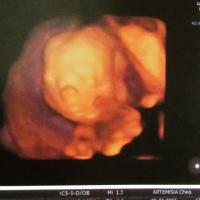

Nagyon cuki kis babaofija van a kisfiadnak.